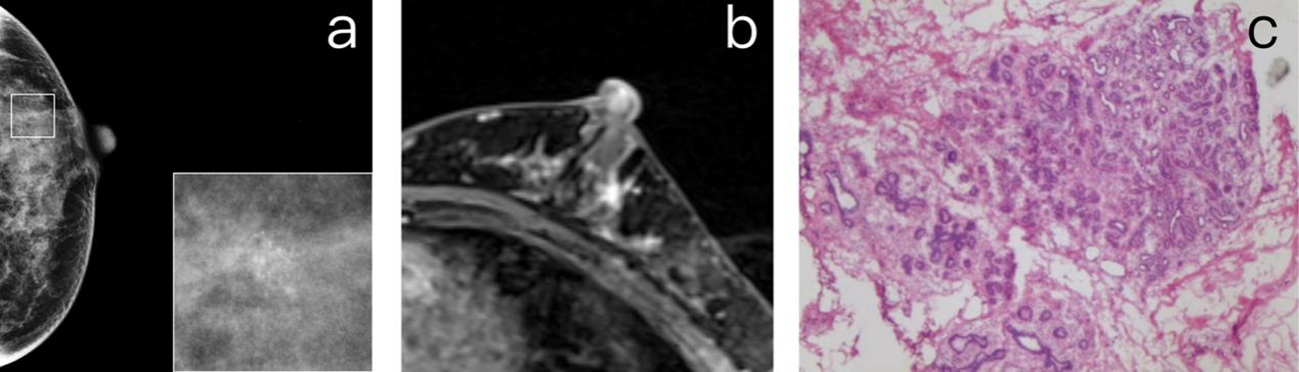

Figure 2

(A) A 47-year-old premenopausal female who underwent screening mammography shows grouped amorphous microcalcifications in the upper outer quadrant of the left breast. (B) Postcontrast DCE-MR images of the left breast show regional NME correlated to the location of calcifications. The patient was diagnosed as BI-RADS 4. (C) The patient underwent breast-conserving surgery. The histopathology shows a grade 2 DCIS.